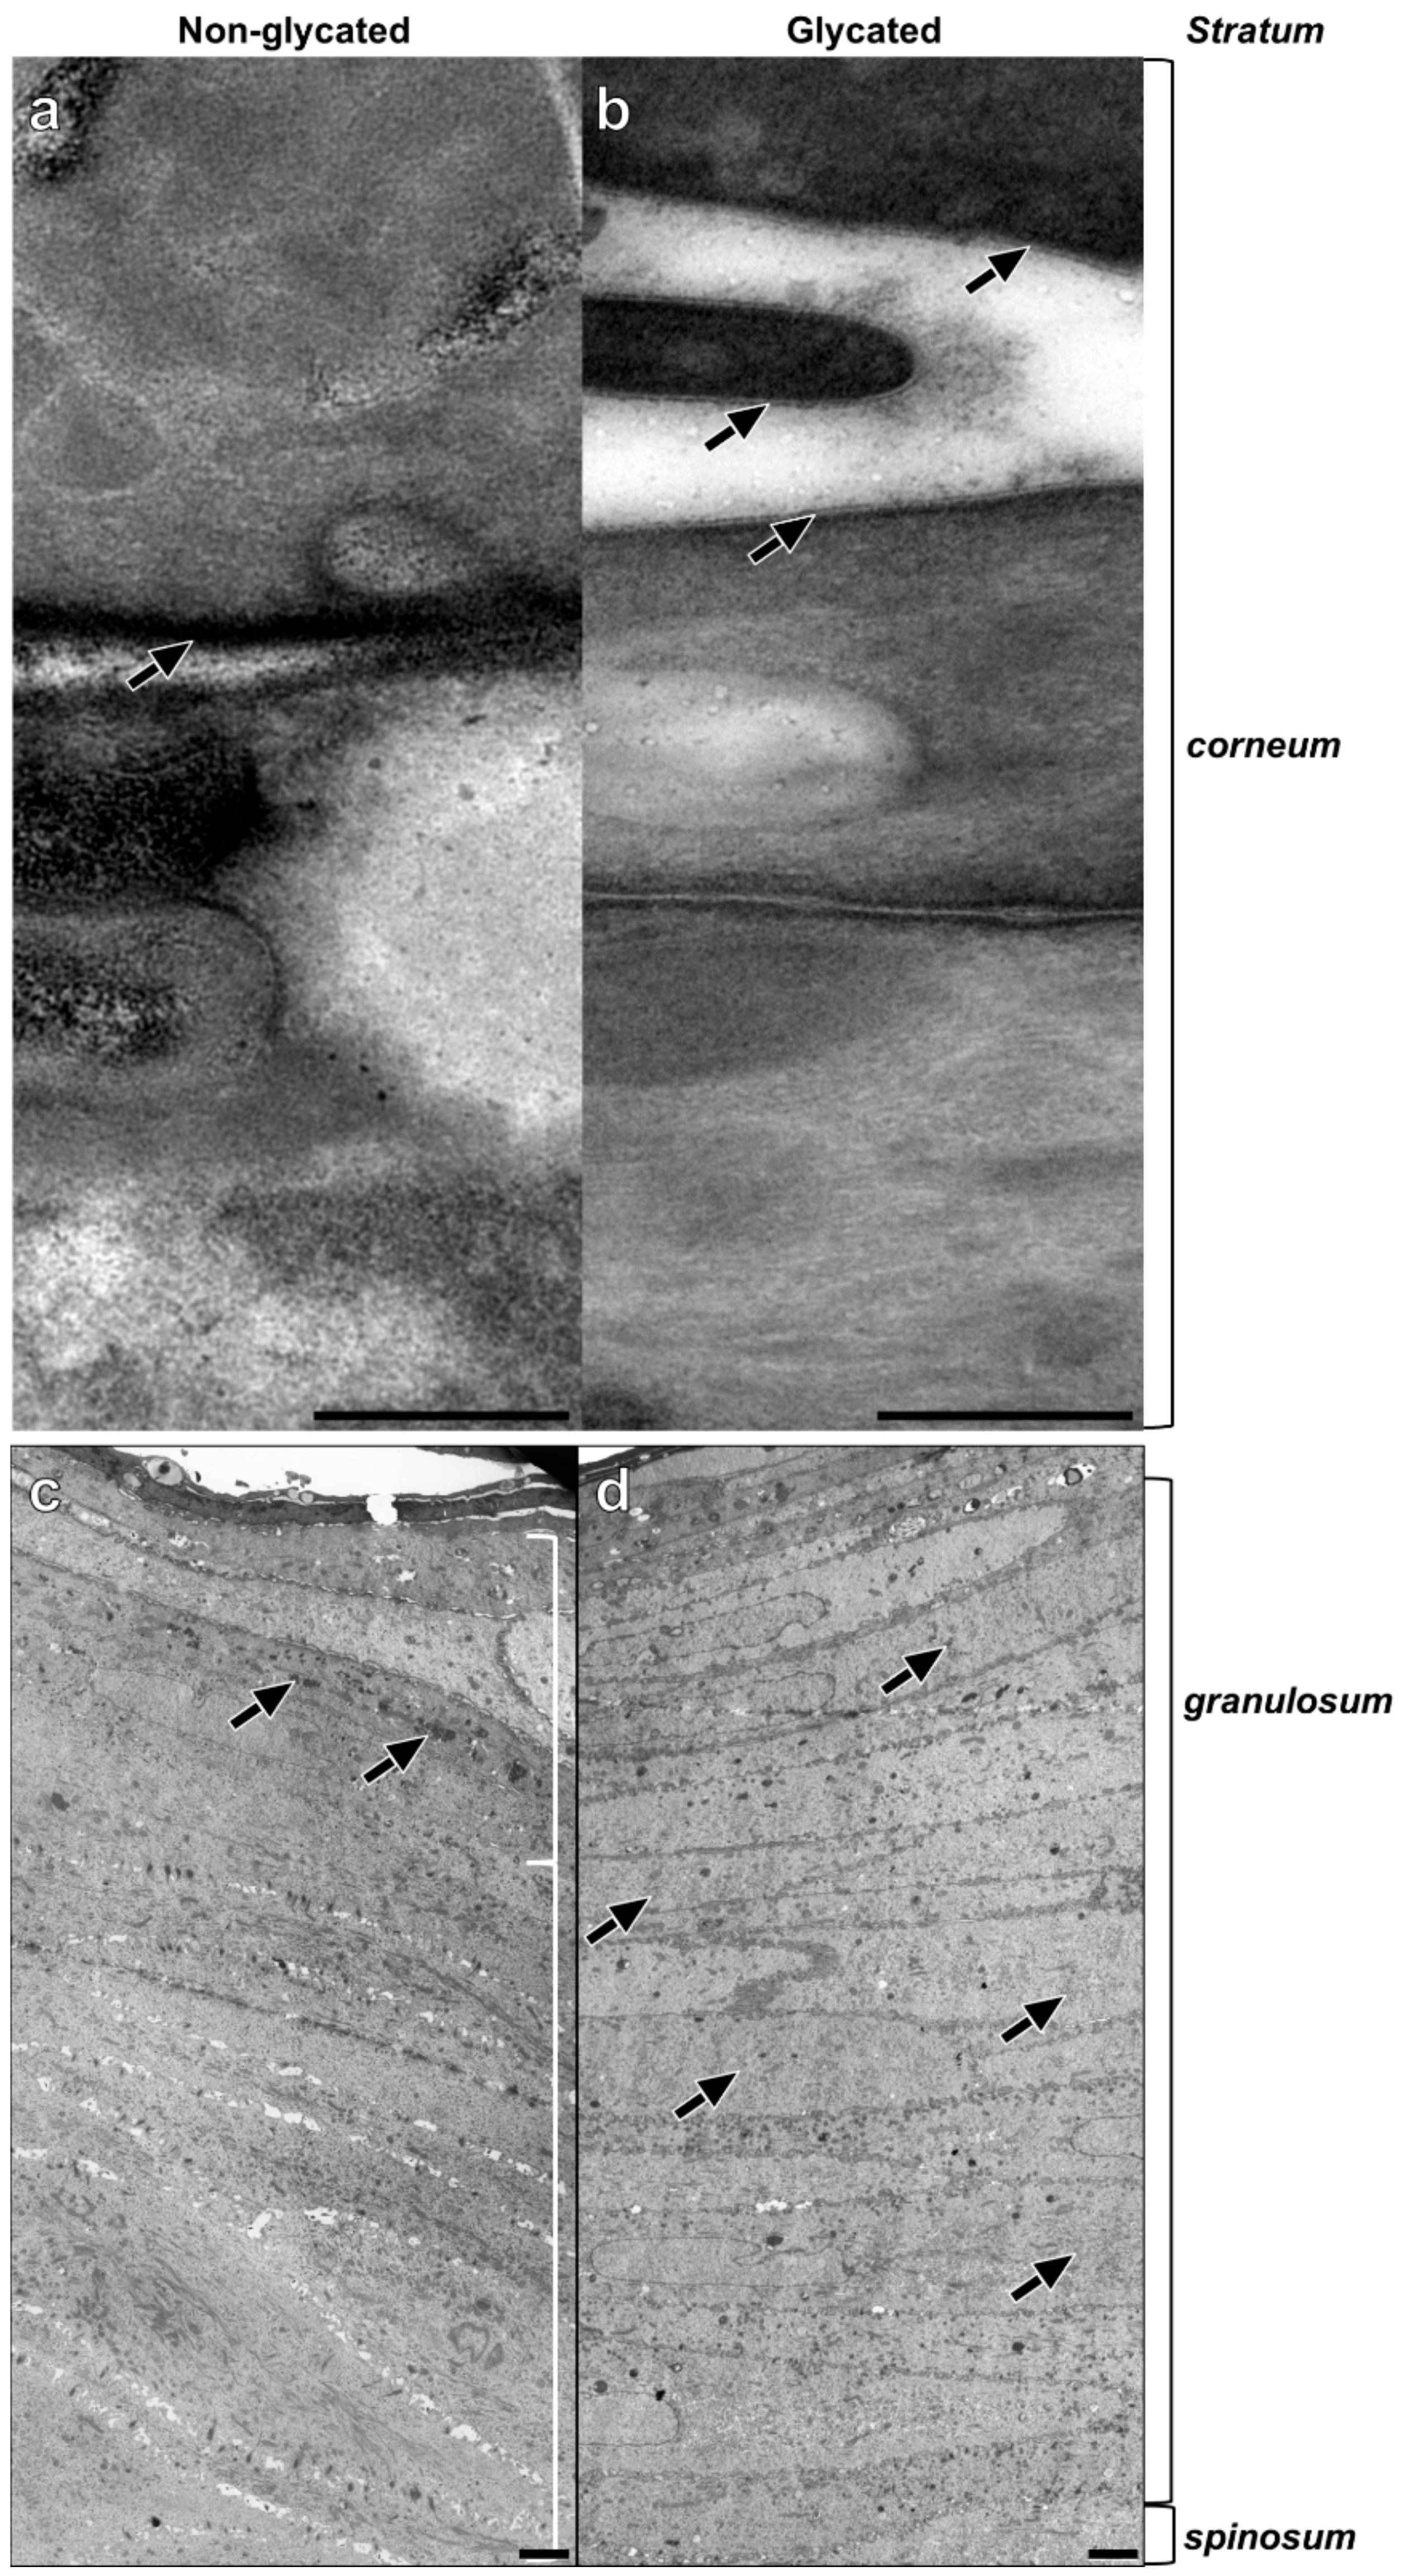

TEM analysis of the epidermal compartments revealed striking differences between glycated and non-glycated RHS, especially in the thickness and number of cell layers of the stratum granulosum (Figure 4c,d).

Figure 4.

Epidermal ultrastructure of (a,c) non-glycated and (b,d) glycated RHS. (a) Lipid lamellae within the intercellular space of neighboring corneocytes. (b) Fine lines of the intercellular lipids are clearly visible (arrows). (c) Packed keratohyalin granule-like structures (arrows) in the upper layers of the viable epidermis, indicating the stratum granulosum. (d) The stratum granulosum dominates the epidermal compartment. Fine electron dense material evenly disseminated within the cytoplasm of the keratinocytes (arrows). Pictures are representative for two batches. (a,b). TEM, bar = 0.25 µm; (c,d) TEM, bar = 2.5 µm.

The stratum spinosum of non-glycated RHS contained seven layers on average, comprising a decidedly greater proportion of the viable epidermis than in glycated RHS. The stratum granulosum of non-glycated RHS constituted on average three layers of tightly packed cells with mitochondria and large, irregularly shaped keratohyalin granules (Figure 4c).

In the glycated RHS, the keratinocytes in the basal layer were columnar and cuboidal shaped. The stratum spinosum contained four layers on average, while more than 20 cell layers were designated as stratum granulosum, comprising the majority of keratinocytes within the epidermis of glycated RHS. These keratinocytes were increasingly flattened and densely packed. Atypical keratohyalin granules were present as fine, disseminated electron dense material. Although this material slightly differed from the keratohyalin granules in non-glycated RHS, we regarded this material as small keratohyalin granules. Moreover, the number of mitochondria and other cell organelles decreased, especially in the apical parts of the stratum granulosum (Figure 4d).

In both constructs, the keratinocytes transformed into flat, tightly packed corneocytes, attaching themselves to each other via corneodesmosomes. Stratum corneum of non-glycated RHS consisted of seven layers of corneocytes, which increased to twelve layers in glycated RHS. While a cornified envelope was developed in both types of RHS, the lipids in the glycated models were slightly clearer to visualize and distinguish from the plasma membrane than in non-glycated RHS (Figure 4a,b). This deviating ultrastructure points to different lipid organization in non-glycated and glycated RHS.

Moreover, we observed enhanced keratinocyte proliferation in glycated RHS, indicated by the increase in total epidermal thickness (Figure 2 and Figure 4). In our study, more than 20 cell layers corresponded to the stratum granulosum, containing disseminated electron dense material, which we interpreted as atypical keratohyalin granules. Absent keratohyalin and increased stratum granulosum height were described in particular types of psoriatic epidermis [28,29]. The increased thickness of the stratum granulosum indicates defective differentiation of the transitional located keratinocytes of the stratum granulosum and thus resembles parakeratotic psoriatic skin. The increased expression of loricrin was well in accordance with the abundant fine granula in the epidermal compartment of glycated RHS (Figure 5) [30]. In fact, keratinocytes with atypical keratohyalin granules dominated the epidermal compartment as “stratum intermedium” of glycated RHS. Furthermore, we observed changes in the intercellular space of the stratum corneum (Figure 4), which intrigued us to investigate the stratum corneum lipid order and profile.